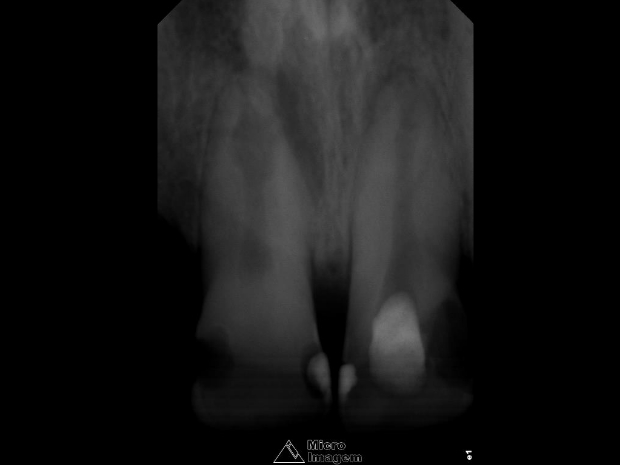

O mesmo relatava histórico de trauma dental na infância, sendo que previamente foi submetido a uma intervenção de urgência no elemento 21 por outro profissional, visto que se apresentava com edema e dor na região apical. Pela presença de fístula nesta região, foi realizado rastreamento na mesma, sendo a mesma oriunda do elemento dental 21 (figuras 2 e 3).

- Figura 2

- Figura 3